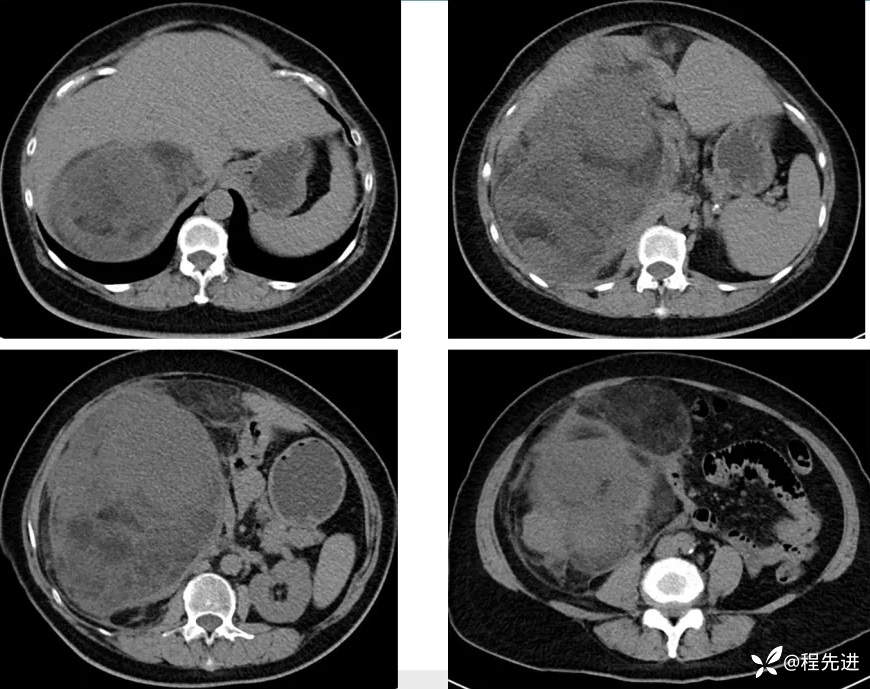

【主诉】:腹胀2月余,发现腹腔占位10天

【现病史及既往史】:患者2月余前出现腹胀,胃反酸,无寒战发热胸闷胸痛、恶心呕吐、腹痛腹泻等不适伴随症状。10天前患者自查发现腹腔占位

【检查】: